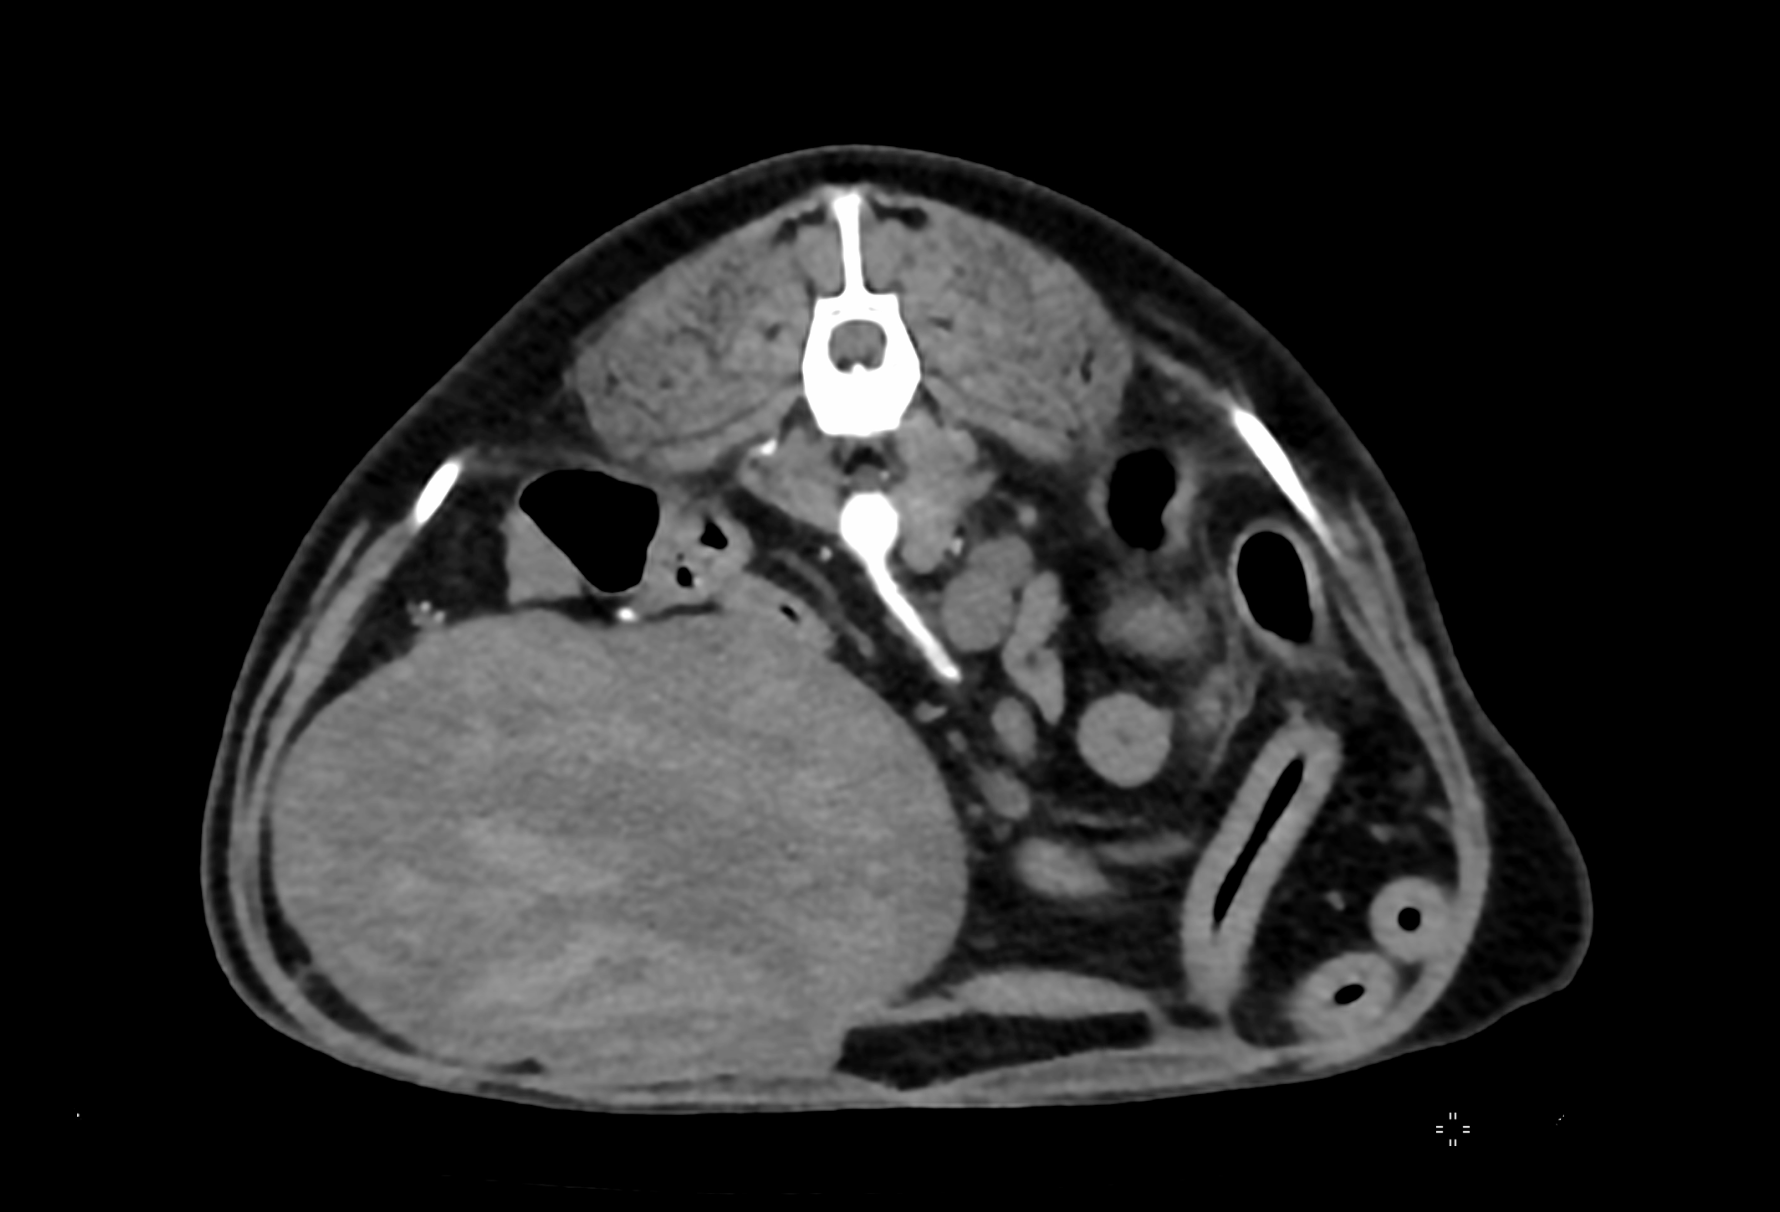

そしてその麻酔前検査(MRIは麻酔が必要となります)をしたところ、X線(レントゲン)検査にてお腹の中に巨大な腫瘍があることがわかりました。

緊急で詳細な検査を実施したところ、腫瘍はおそらく脾臓を起源としているだろうこと、また心臓にも腫瘍があることが残念ながら診断されました。

通常であれば、14歳のわんちゃんに手術を勧めることはあまりないのですが、今回の脾臓の腫瘍が破裂すると突然死を起こすこと(6~8cmもありました)、心臓の腫瘍が脾臓の腫瘍の転移ではなく別物の腫瘍であること(こちらは比較的進行がゆっくりな腫瘍と診断されました。)から、急遽CTにて全身の転移などがないことを確認し、開腹手術にて脾臓を摘出しました。